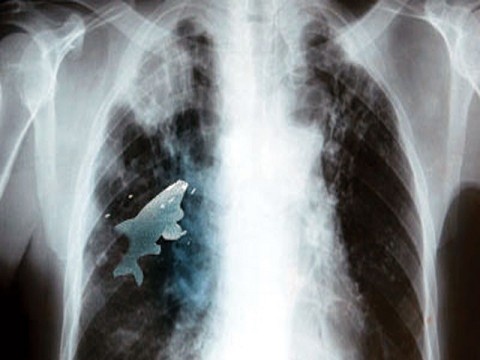

La imagen que acompaña esta noticia curiosa, parece haber sido editada o retocada fotográficamente, pero no lo es. Se trata de un pez en el pulmón de un niño. El pez vivo quedó atrapado en el interior del pulmón de un niño de 12 años.

No era la primera vez que Anil y sus amigos jugaban a eso, pero esta vez fue distinto, el pez no fue a parar al estómago, sino lo que aspiró y terminó en el pulmón izquierdo a través de la tráquea, informa The Nation, de Pakistán.

Así que el jovencito empezó a tener dificultades para respirar y fue llevado al hosital de su localidad. Los médicos verificaron que los niveles de oxígeno en su sangre habían bajado, lo que lo exponía a un serio peligro.

Anil fue sometido a un intervención quirúrgica de emergencia que duró 45 minutos. Cuando los médicos extrajeron el pez al que llegaron a través de la broncoscopía, todavía estaba vivo.